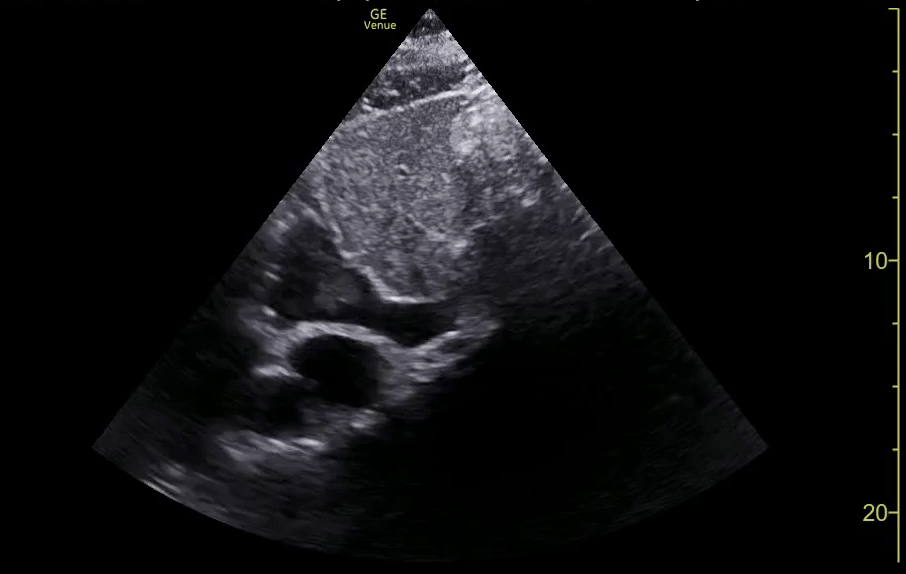

Intussusception